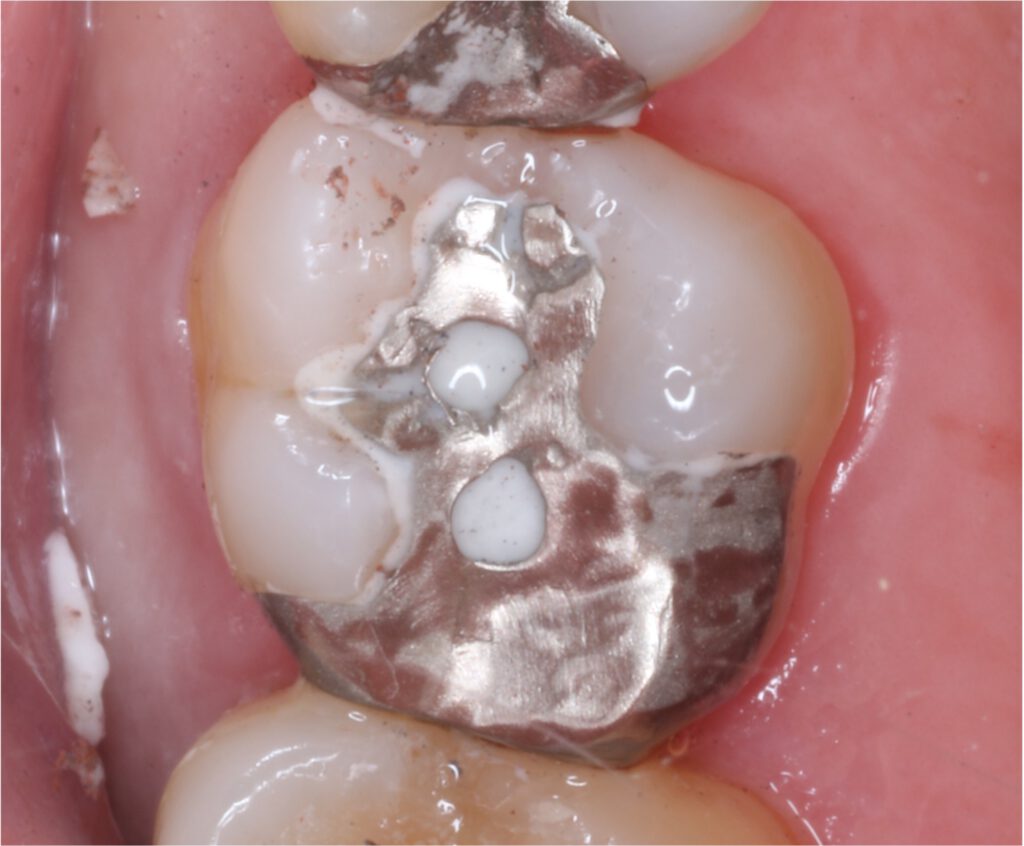

01精密根管治療

「抜くしかない」と言われた歯でも、根の中の感染を適切に抑えられる治療技術があれば、歯を残せる可能性があります。根管は非常に細く複雑で、わずかな取り残しが痛みや腫れの再発につながることもあるため、当院では必要に応じてCTやマイクロスコープを活用し、原因を見極めながら丁寧に処置を進めます。

大杉歯科医院が大切にしているのは、早く終える治療ではなく、歯を守る治療。津市で、できるだけ天然歯を残したい方の選択肢になれるよう取り組んでいます。症例1

症例2

- 治療名

- マイクロスコープとラバーダムを使用した精密根管治療

- 患者様

- 40代女性

- 執刀医

- Dr. 大杉

- 治療期間

- 3ヶ月

- 治療費

- 精密根管治療:130,000円(税込)

築造:40,000円(税込)

セラミック:130,000円(税込) - リスク

- 治療中〜治療後に痛みが出る場合あり

再感染・治癒不全の可能性

補綴後も定期管理が必要